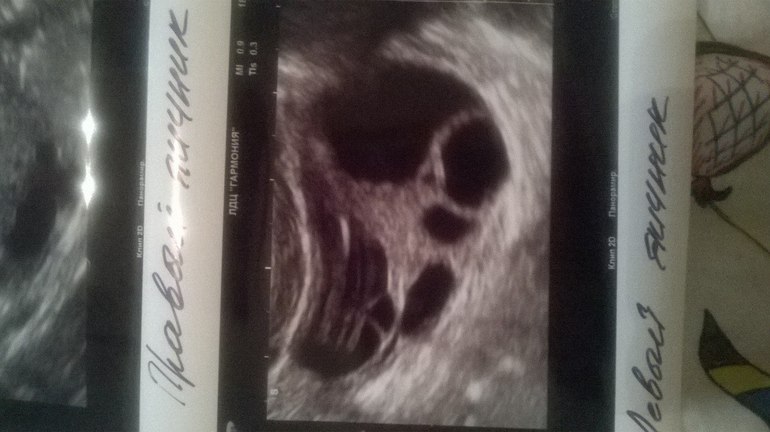

ой вот фото,но я в нем бум-бум(